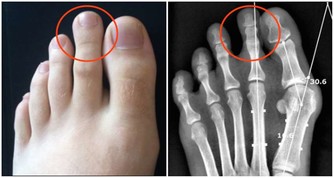

痛風,這個醫學名詞理解起來不難!

先說“痛”字,主要是發病時患者的關節會產生劇痛,就像身體的某個部位長出刺來一樣,想想就內心就覺得疼啊!再說“風”,這說明痛風也就是痛一會兒,時間不是很長,就像一陣風刮過之後,就沒了!